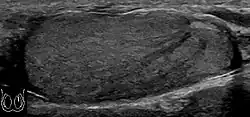

Patients with testicular lymphoma are usually old aged around 60 years of age, present with painless testicular enlargement and less commonly with other systemic symptoms such as weight loss, anorexia, fever and weakness. Bilateral testicle involvements are common and occur in 8.5% to 18% of cases. At sonography, most lymphomas are homogeneous and diffusely replace the testis [Fig. 7]. However focal hypoechoic lesions can occur, hemorrhage and necrosis are rare. At times, the sonographic appearance of lymphoma is indistinguishable from that of the germ cell tumors [Fig. 8], then the patient's age at presentation, symptoms, and medical history, as well as multiplicity and bilaterality of the lesions, are all important factors in making the appropriate diagnosis.